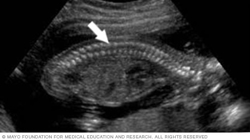

This image is of a fetus's spine. It's one of the easier structures to recognize when viewing a fetal ultrasound.